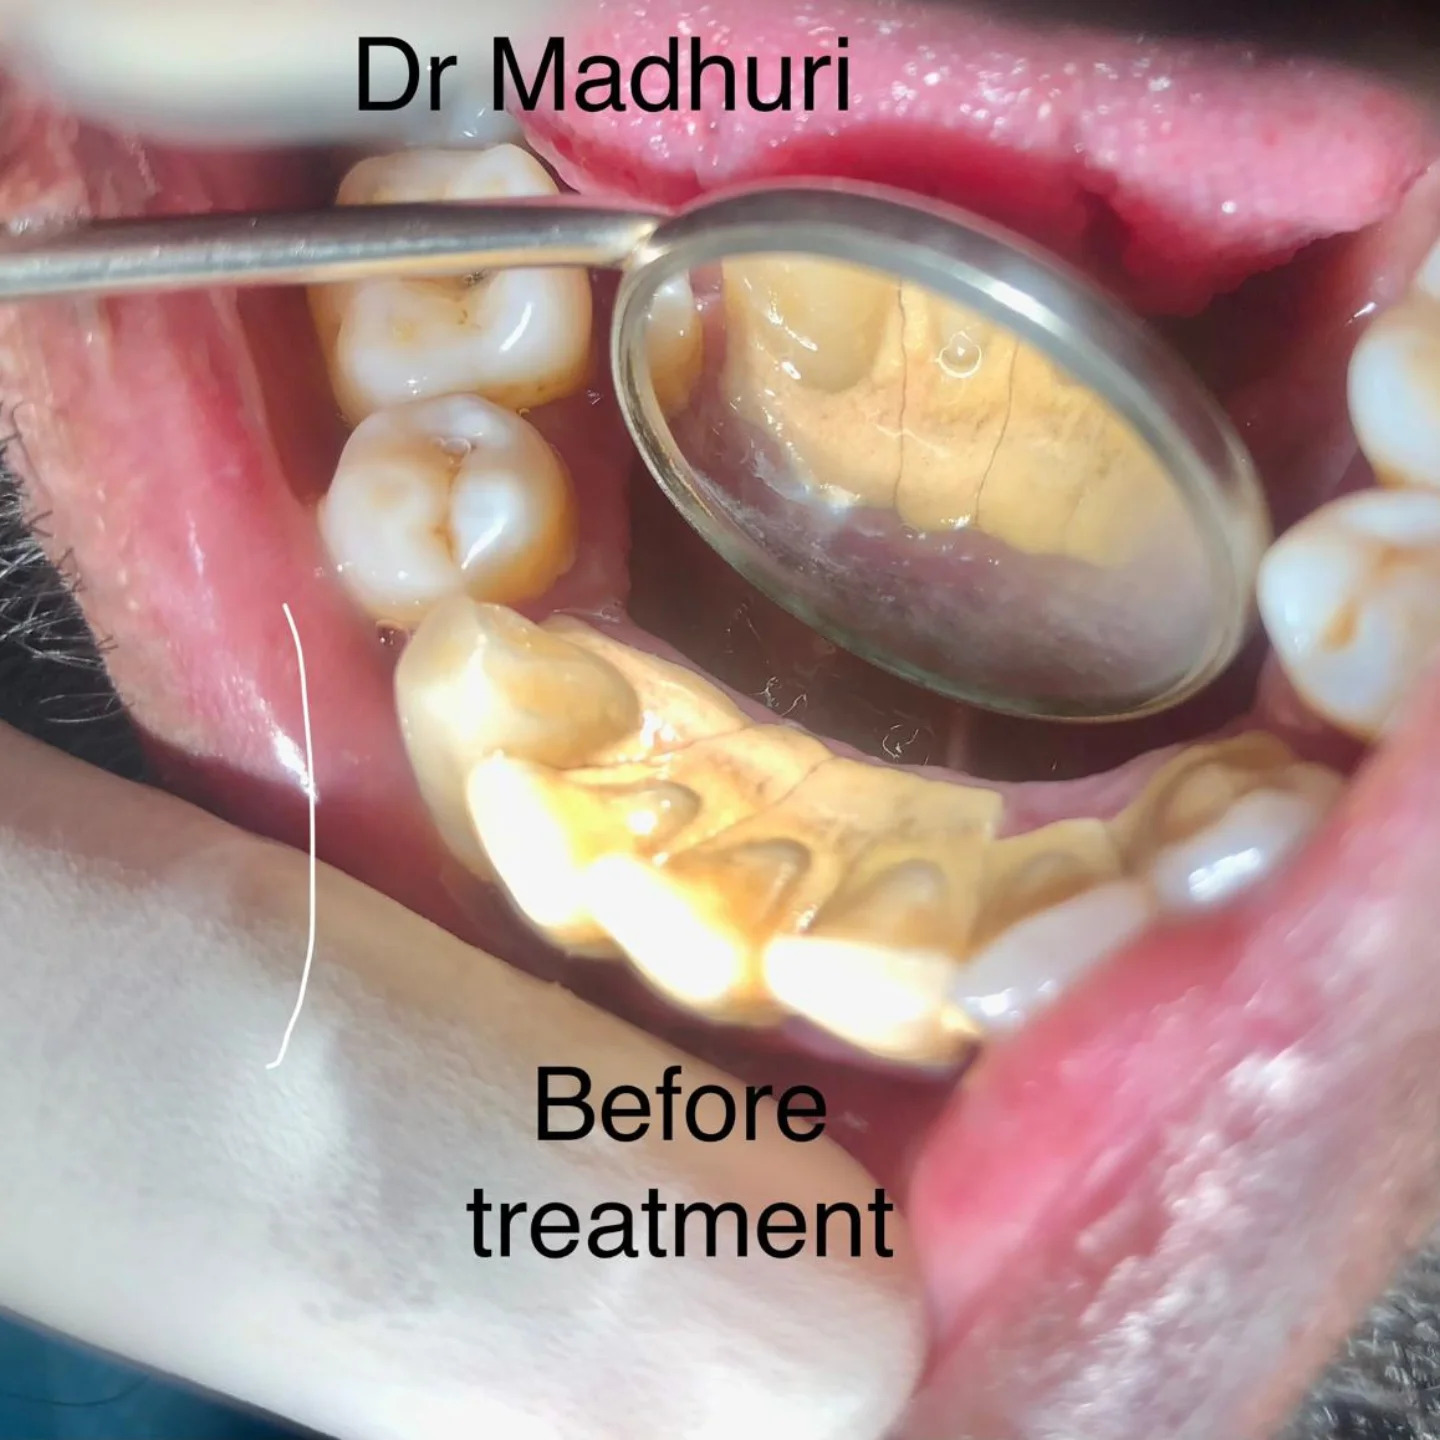

Explore Our Clinical Dental Gallery

Welcome to our official treatment gallery, showcasing the real results, smile transformations, and advanced dental care delivered by Dr. Madhuri. We believe that a picture is worth a thousand words when it comes to the art and precision of modern dentistry. Review our comprehensive visual portfolio below to see how our dedicated care helps patients achieve healthy, beautiful, and confident smiles.